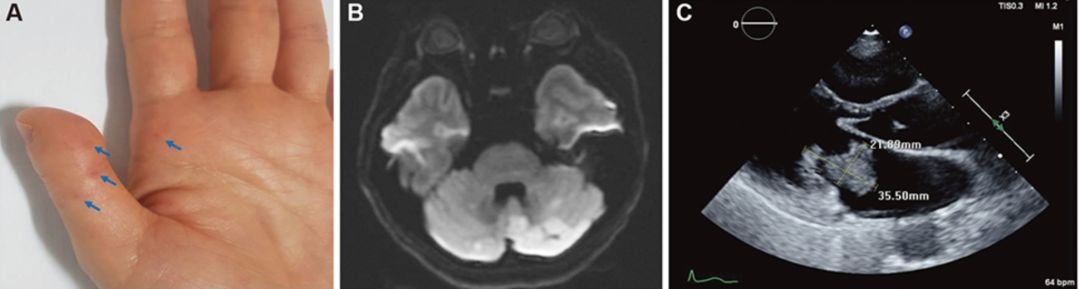

患者50岁,女,突发构音困难,眩晕、左侧肢体外旋,体检发现双手掌侧小(<1毫米)无痛性皮疹,患者12年前小脑后下动脉区梗死。患者12年前在小脑后下动脉区域有梗塞。既往心脏3.5厘米的粘液瘤术后9年。

答案:长期复发性心脏粘液瘤相关复发性脑梗死。

➤ A:左手掌面Janeway病变。在拇指和手掌的掌侧有数个红色斑皮疹(箭头)。

➤ B:DWI可见双侧小脑均多处弥散受限,多为小脑后下动脉区。

➤ C:患者经食管超声心动图示左心房3.5 cm大小粘液瘤。

Carney综合征是一种罕见的遗传性疾病,最早由J Aidan Carney在1985年首先描述。作为一种罕见的多发性内分泌腺瘤综合征,其特征为皮肤和黏膜表面出现独特的色素沉着、心脏和心脏外出现粘液性肿瘤,以及多发性内分泌肿瘤。多发性内分泌肿瘤、皮肤及心脏累及是本病的基本特点。心脏粘液瘤是猝死的重要原因。其临床表现复杂多样,缺乏特异性,误诊率较高。全身症状主要有嗜睡、疲劳、发热、食欲低下、痛性红斑、体重减轻等。诊断困难时,经食管超声和MRI有一定帮助。